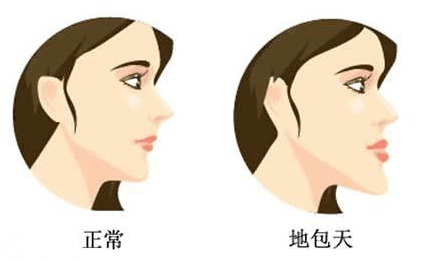

“地包天”的形成因素有很多,最主要的就是遗传因素,但是后天的环境和习惯的影响也不容忽视,主要包括口腔不良习惯和乳恒牙替换期障碍。 “地包天”会影响整个口腔、颜面、颌骨的生长发育,对儿童的身心造成很大影响。

地包天儿童与正常儿童最明显的差别就是前者的面中部平坦或凹陷,下颌前突,主要是由于上颌骨的发育受到了下颌骨的限制引起的。

发现“地包天”的情况,应及时到医院就诊,以明确诊断的病因。不同原因所造成的,其治疗方法也有所区别。